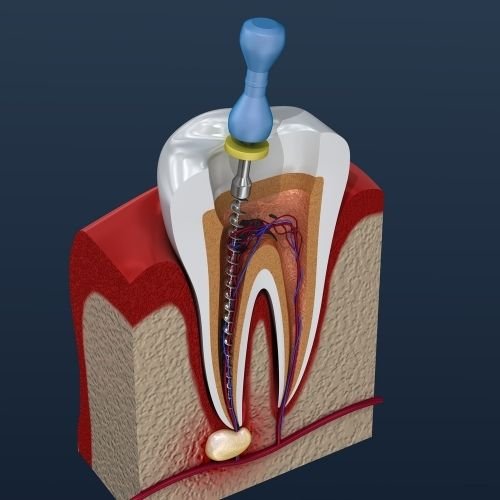

Kök Kanal Tedavisi

🤭Eğer diş çürümesi veya hasarı diş içinde bulunan sinirler ve kan damarlarından meydana gelen çekirdek olan diş pulpasına kadar yayıldıysa, ağızdaki bakteriler buraya girerek enfeksiyona neden olabilir. Bu durum genellikle kök kanal tedavisi ile düzeltilebilir, ancak enfeksiyon çok şiddetli ise ve antibiyotikler veya kanal tedavisi yeterli gelmezse enfeksiyonun yayılmasını önlemek için diş çekimi gerekebilir.